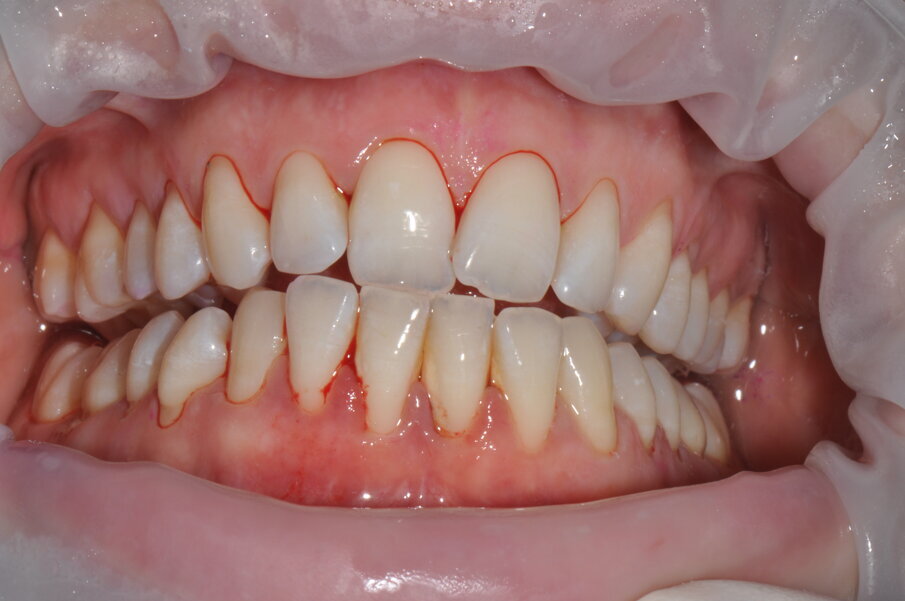

- Applicazione del rilevatore di placca bifasico: permette la distinzione fra i depositi di placca recenti da quelli meno recenti ( 1a-1c);

Figg. 1a-1c - Applicazione del rilevatore di placca che verrà usato come guida durante la terapia, nel versante vestibolare (1a), palatale (1b) e linguale (1c). Si noti lo scarso livello di igiene orale domiciliare e l’assenza di utilizzo dei presidi interdentali.